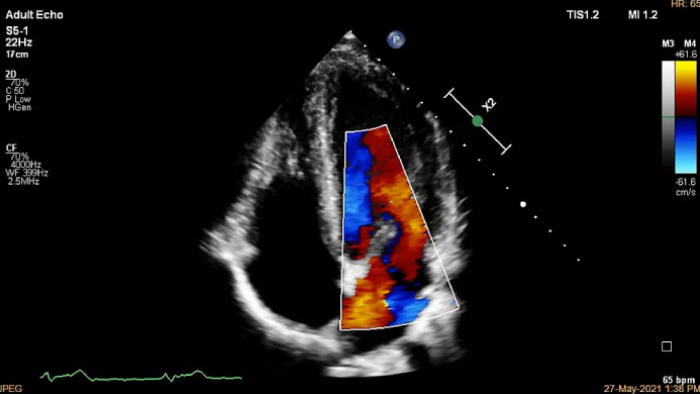

Cardiovascular Ultrasound

Increase diagnosis confidence and clinical efficiency through superior image quality, advanced quantification tool and automation technology.